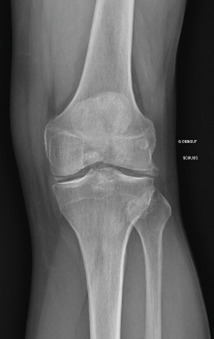

La forme pseudorhumatoïde est rare (5 %), simulant une polyarthrite rhumatoïde (diagnostic différentiel), avec parfois des signes systémiques d’inflammation (élévation de la vitesse de sédimentation et de la CRP). Le diagnostic repose sur la mise en évidence des cristaux de PPC. La radio peut mettre en évidence des calcifications des cartilages articulaires (fig. 6) et des fibrocartilages (fig. 7, 8, 9 et 10). L’échographie (plus sensible) peut mettre en évidence des dépôts de PPC, qui apparaissent comme une fine bande hyperéchogène au sein des cartilages hyalins et comme des points scintillants dans les fibrocartilages ou dans la membrane synoviale. Dans l’arthrite chronique à PPC, lespossibilités thérapeutiques sont, par ordre de préférence : colchicine (de 0,5 à 1 mg/j), petites doses de cortisone, parfois les AINS per os (mais leur prescription est souvent limitée par les comorbidités chez les patients âgés), méthotrexate et l’hydroxychloroquine. Il n’y a pas aujourd’hui de traitement « de fond », mais des molécules sont à l’étude.

L’arthrose associée aux dépôts de PPC touche en particulier les genoux, avec une symptomatologie chronique et/ou des accès aigus cristallins. Par comparaison avec l’arthrose idiopathique, elle serait à l’origine d’une symptomatologie plus inflammatoire, toucherait des articulations inhabituelles (radiocarpienne, carpienne, gléno-humérale, médio-pied et arrière-pied, cheville) et serait associée à plus d’ostéophytes et de géodes. Cette arthropathie dégénérative peut s’accompagner de lésions structurales sévères avec disparition rapide de l’interligne (arthropathies destructrices : hanches, genoux, poignets, coudes). Les objectifs et les modalités thérapeutiques sont identiques à ceux d’une arthrose idiopathique. Aucun traitement ne permet la dissolution des cristaux de PPC.